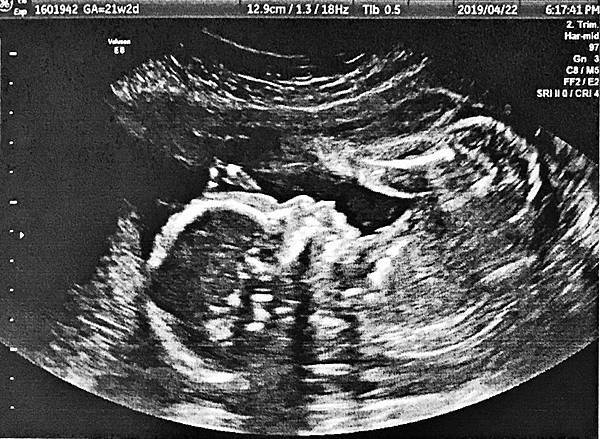

媽媽,你知不知道,他已經很大了啊?!(第一次認識他:18周245g)

一個生命進駐在另一個生命中,一個從未被期待的生命,卻直接被告知的生命,我不禁深深的想到了聖母瑪麗亞 (對不起,我怎麼可能跟聖母比,讓自己被恥笑了,我兒子怎麼可能無緣無故的來),但這般震動的感覺,為何只有女性感受的到,難道沒有人會希望耶穌是由非女人的身體中蘊育出來的嗎?這樣就可以完全斷絕與女人的關係,可惜的是並沒有,耶穌還是從女人的身體中生產出來。這樣非預期的懷孕,即便不是被迫的,我卻也不可能不留下他,因為正因為他是如此非預期,讓我完全沒有丟臉的感覺,在婦產科,一位護理師不願意連名帶姓的叫我,正因為如此,我不敢確定是我而再三確認,她一副難道我不知道,不連名帶姓的叫我,是因為不想讓我有不舒服的樣子,的確,這讓我想了很久才覺得原來如此,還跟她抱歉了一下,但我倒是也不知道,雖然我是狀況外,卻為何要覺得丟臉或不舒服呢?女性的隱私,女性到底要受到什麼樣的保護? 懷孕是如此自然的事,雖然我知道很多人求子不得,但我真正想要的,似乎乃身外之物,更可笑的事,雖然不難取得,但是我好像也得不到,這不是一場賭注,而是一連串的震動,影像的震動,不是超音波影像讓我震撼,而是那心跳的波形,再加上心跳的聲音,我,禁不住的淚流滿面。